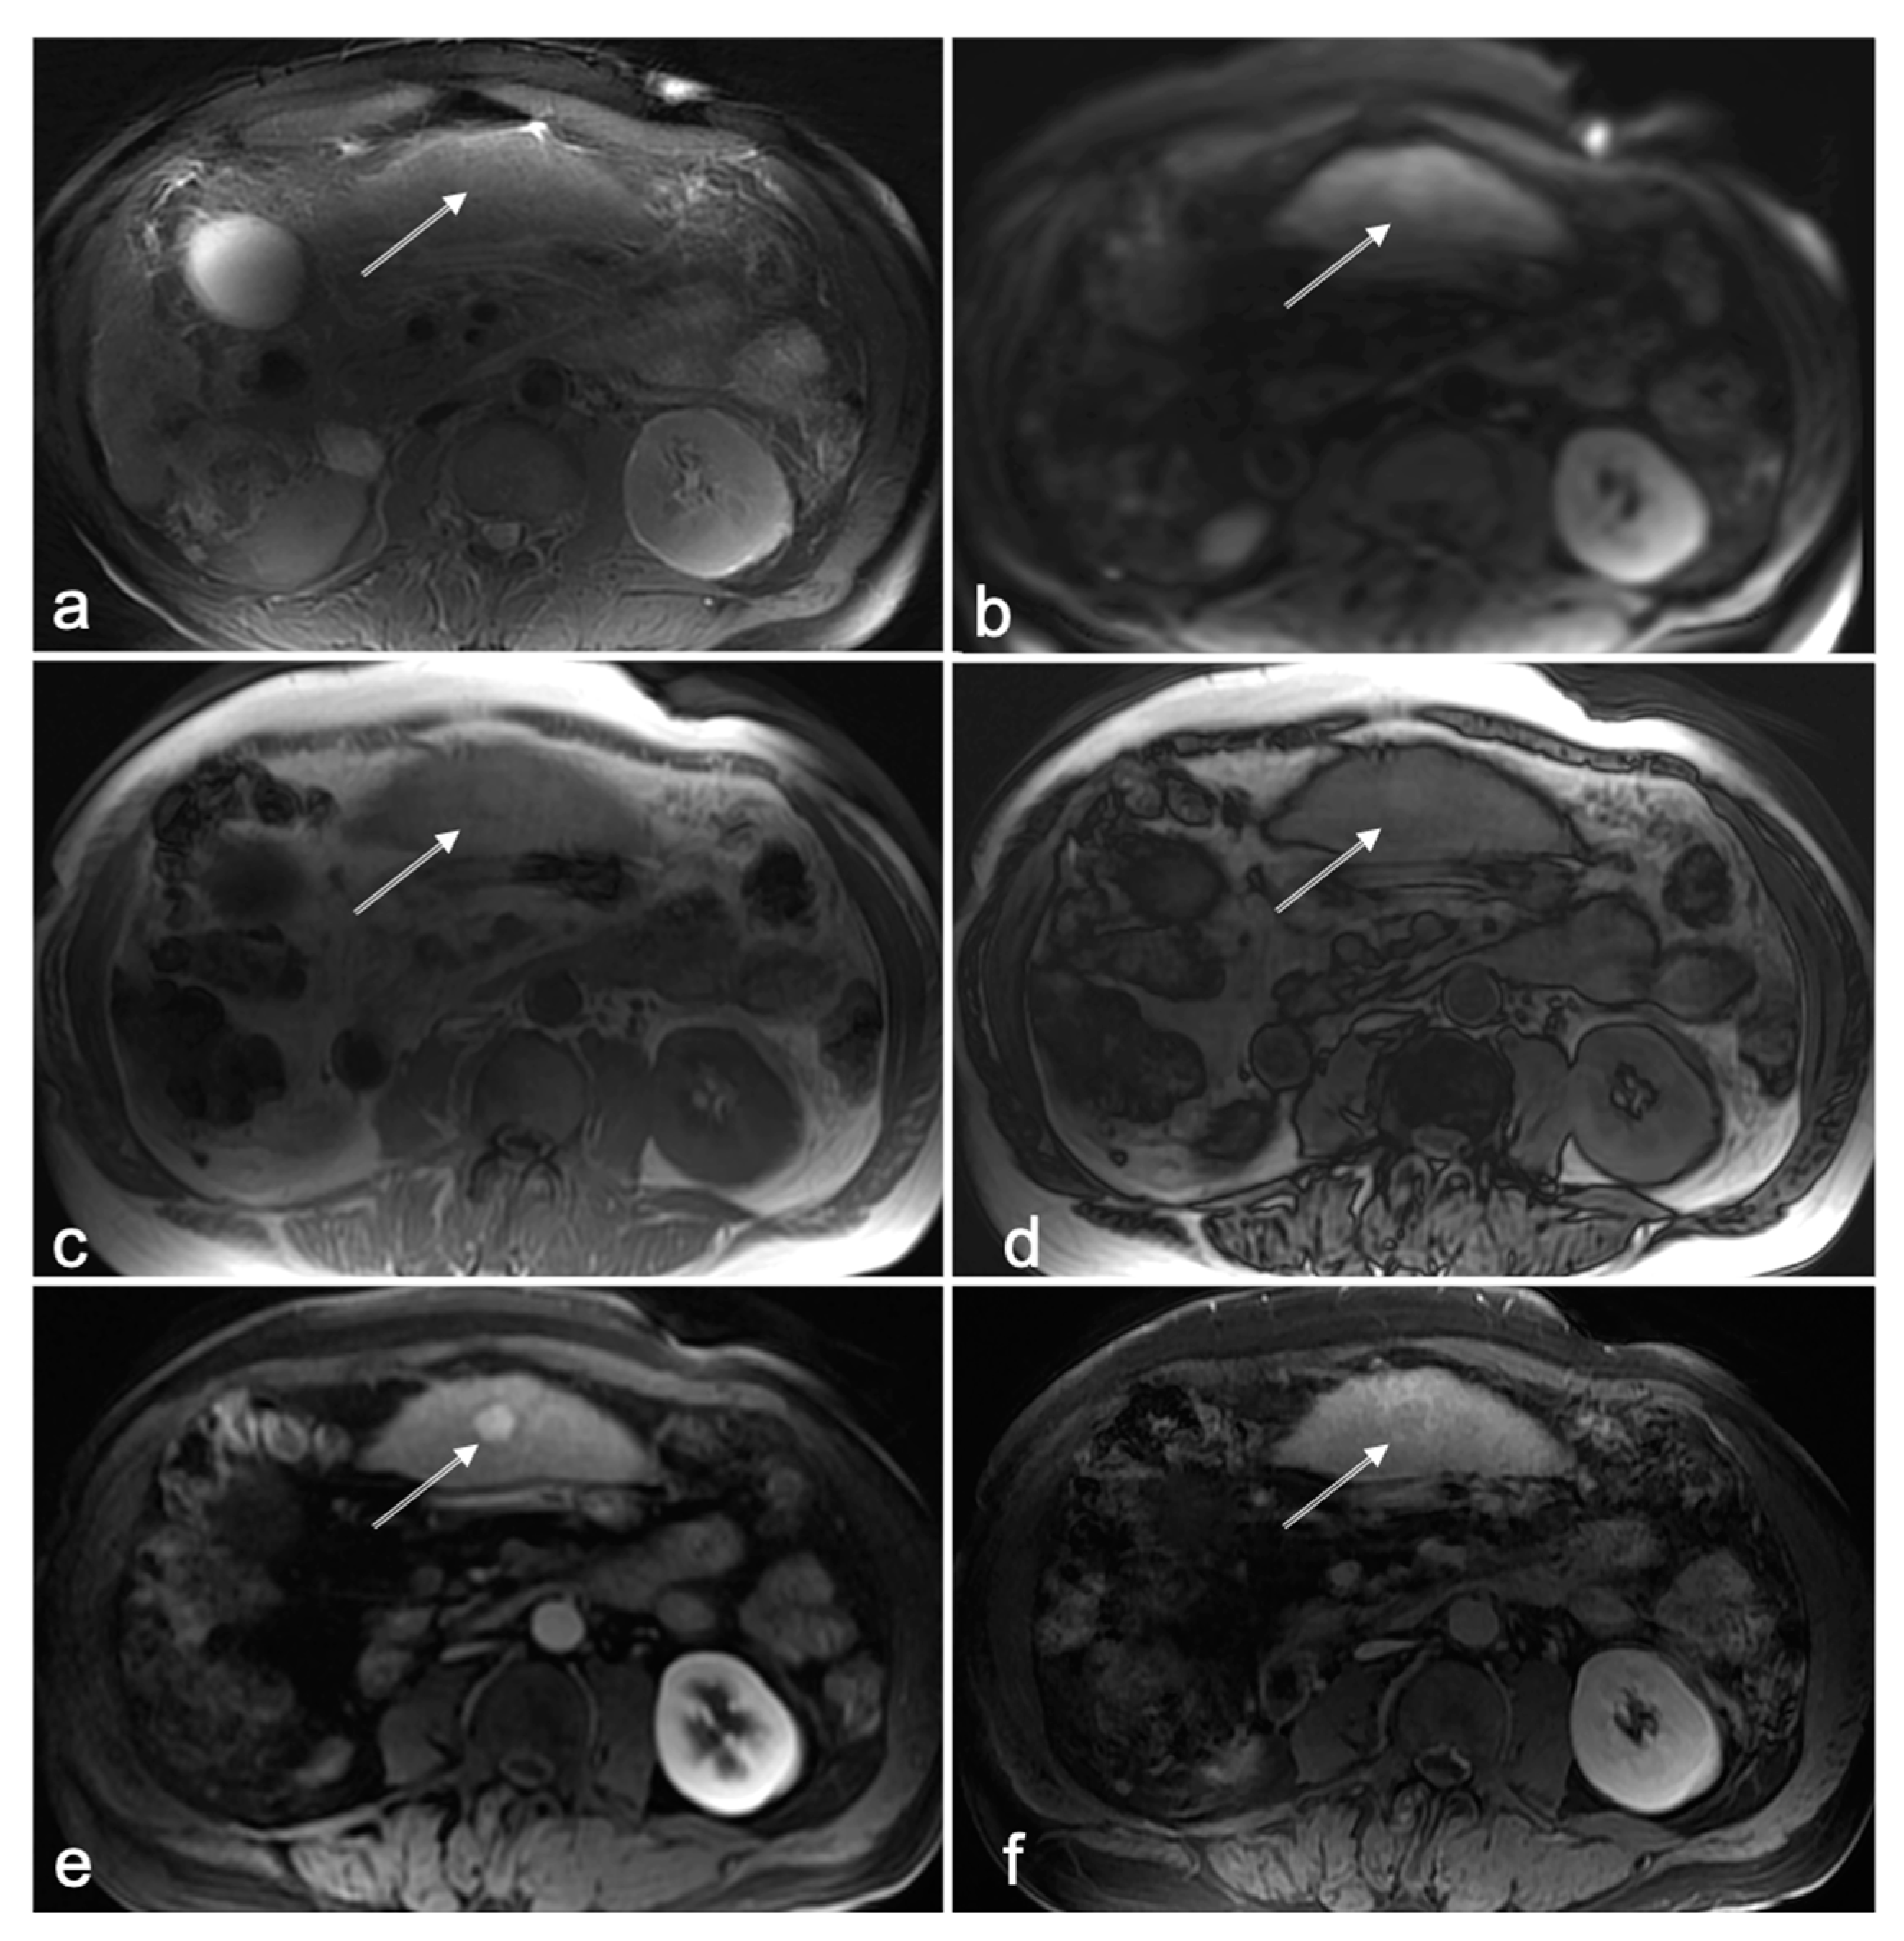

Figure 3.

Seventy-six-year-old male patient with liver cirrhosis caused by NASH. On NC-AMRI initially, no lesion was noted by all three readers (i.e., missed lesion, location of the lesion marked with arrow on (a–f)); axial T2W FS (a), DWI (b = 600 mm/s2) (b), and T1W in-phase (c) and opposed-phase (d). On CE-MRI, a hyper enhancing lesion in segment 3 is clearly identified (arrow) on T1 arterial phase (e) with delayed washout and capsular enhancement (f), compatible with an Li-RADS 5 lesion. Upon review by consensus after data analysis, the readers agreed that the lesion was not discernable on T2W FS (a), and merely very slightly hyperintense on DWI (b) and T1W in-phase (c) and opposed-phase (d) images. It was concluded that the lesion was missed in this patient on NC-AMRI owing to a sub-optimal image quality of the left liver lobe with an overall lack of signal intensity on DWI.